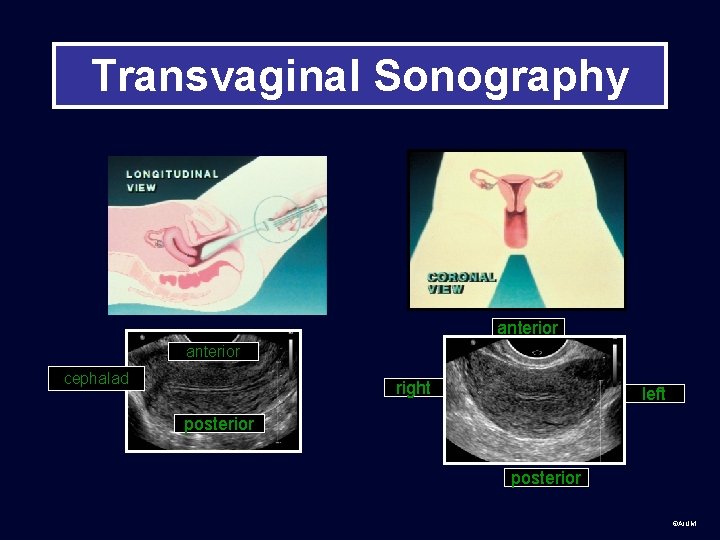

Transvaginal Sonography anterior cephalad right left posterior ©AIUM

Use all the information from the labeling that you are given to orient yourself to anatomy Long= longitudinal, usually sagittal relative to body. Convention: patient’s head to left of screen. Trans=transverse, usually axial relative to body. Convention: patient’s right side to left of screen. ©AIUM